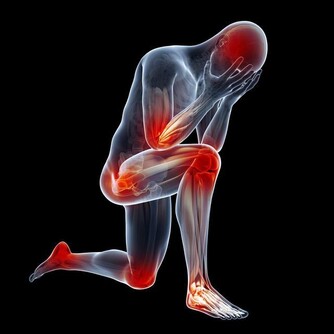

氣溫驟降時,腦血管疾病發病者明顯增加。劉霞發病時,正好遇到兩大誘因,一是天氣轉冷,二是深夜用熱水泡腳,都可能令血管受到強烈刺激,一定程度上誘發疾病。因此,有腦血管基礎性疾病的市民,近期應注意防寒保暖,避免身體遭受冷暖刺激。少用過熱的水洗澡、泡腳,少喝酒,避免情緒激動。同時,還應定時對身體進行全面檢查。